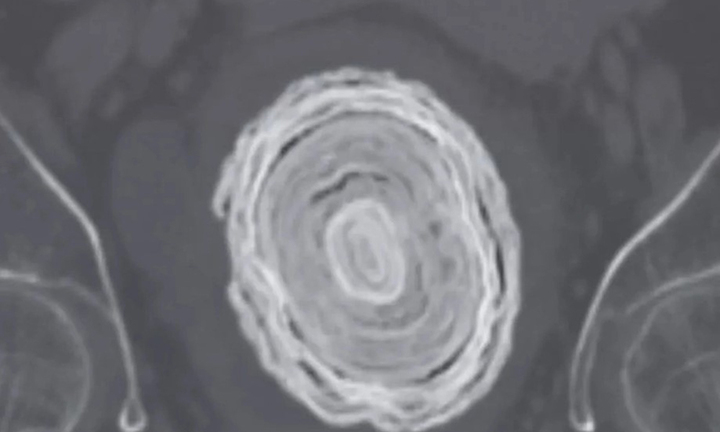

Các bác sĩ phát hiện một viên sỏi bàng quang khổng lồ, to bằng quả bóng chày, khi siêu âm cho một phụ nữ 72 tuổi có triệu chứng đau đớn và tiểu ra máu.

Chàng trai 32 tuổi, liệt vận động quá nửa cuộc đời nay lại trong tình trạng sức khỏe cực kỳ nguy kịch sau khi bị nhiễm trùng tiết niệu do sỏi.

Bị bí tiểu, bụng đau dữ dội, cụ ông 72 tuổi vào viện cấp cứu và được bác sĩ phát hiện một ống dẫn tiểu cũ đặt dẫn lưu từ bàng quang.